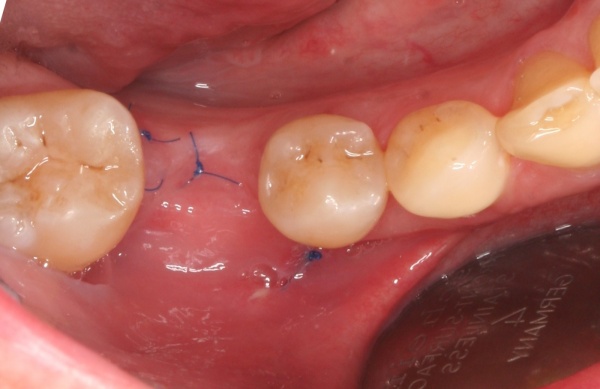

Eine weichgewebschirurgische Vorbereitung des zukünftigen Implantatlagers bereits zu diesem Zeitpunkt ist häufig ratsam. Dazu gehört unter anderem wie in diesem Bildbeispiel die Verbreiterung der Zone keratinisierter Gingiva. Eine gedeckte Einheilung des Implantates wird somit wahrscheinlicher. Therapeutisch kompliziertere Eingriffe nach der Freilegung oder sogar erst nach prothetischer Versorgung werden vermieden (Abb. 5a/b).